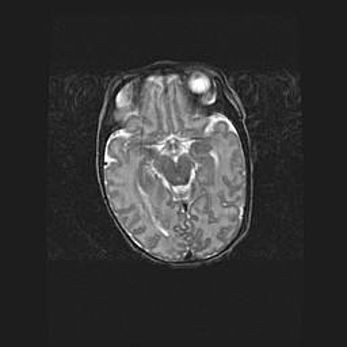

Открытая гидроцефалия.

Возраст: 9 месяцев 12 дней

Вес: 6800 г

Пол: мужской

Окружность головы: 41,5 см

Срок гестации: 28 недель

Гидроцефалия головного мозга у новорожденных имеет характерный признак: опережающий рост окружности головы приводит к визуально хорошо определяемой гидроцефальной форме сильно увеличенного в объёме черепа. Детские неврологи определяют следующие симптомы гидроцефалии у грудничков: выбухающий напряжённый родничок, частое запрокидывание головы, смещение глазных яблок к низу.